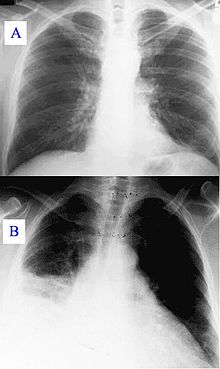

wikipedia.org/Muestras de diagnóstico con rayos X: a) Pulmón sano. b) Pulmón con neumonía.